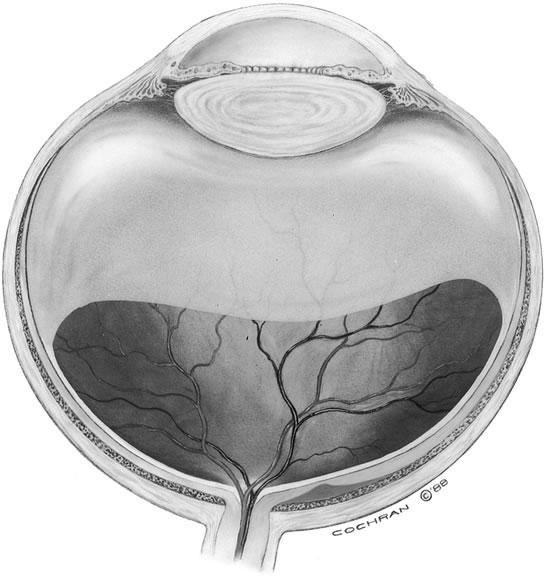

The vitreous of the normal human eye weighs approximately 4 g and occupies a volume of almost 4 ml. The precise weight and volume vary with the age and the size of the eye. The vitreous body is spherical with a depression in the anterior surface, the patellar fossa, corresponding to the posterior surface of the crystalline lens. Larsen1 ultrasonically measured the axial length of the vitreous body in 926 children. He noted that the mean value in newborns was 10.48 mm in boys and 10.22 mm in girls. A sex difference of 0.23 to 0.38 mm greater mean length was noted in males at birth and persisted throughout the growth period. By the age of 13 years, when the axial growth of the vitreous body is essentially completed, the average length was 16.09 mm in males and 15.59 mm in females. Larsen further noted that the relationship between vitreous length and refraction was already established by 1 year of age.

The vitreous body interfaces with a number of ocular structures through the vitreous cortex (Fig. 1). The vitreous cortex extends anteriorly from the vitreous base to form the anterior vitreous cortex and posteriorly to form the posterior vitreous cortex. Recently, the clinical importance of vitreous cortex has become increasingly apparent. The vitreous cortex has been implicated as a primary factor in a variety of vitreoretinal disorders, including retinal breaks, proliferative vitreoretinopathy (PVR), anterior hyaloidal fibrovascular proliferation, macular holes, and epiretinal membranes.

The anterior vitreous cortex or anterior hyaloid is the anterior surface layer or condensation of the vitreous body. There is no specialized membrane that constitutes the anterior vitreous cortex, but instead there is a greater density of collagen fibrils. Microscopically, the framework of collagen fibrils that run throughout the vitreous body ends in an interwoven network to form the anterior vitreous cortex. The superficial fibrils tend to run parallel to the surface in this region. The smooth surface and membrane-like appearance are due to the lamellar distribution of the cortical fibers and the associated highly polymerized mucoproteins.4,5 Anatomically, the anterior hyaloid forms the posterior limits of the posterior chamber. This portion of the vitreous cortex functions in the physiologic communication between the vitreous cavity and the aqueous humor. The anterior surface of the vitreous body separates from the pars plana approximately 1.5 mm anterior to the ora serrata. It extends medially to contact the lens posterior to the lens equator. Thus, the anterior hyaloid is in contact with the ciliary processes and the lens zonules, as well as the posterior lens capsule. The vitreous attaches to the lens capsule in a ring-like manner, forming the hyaloideocapsular ligament of Wieger. This ligament is believed by some to be synonymous with the attachment ring of the posterior zonular fibers.4 The circular area of attachment measures approximately 9 mm in diameter and is especially firm in younger persons or after intraocular inflammation.5 In this circular area the anterior hyaloid is thickened. Central to the attachment of Wieger's ligament (also known as Egger's line), the vitreous lens attachment is less pronounced and appears to be due to surface tension. This central area contains a potential space within the 9-mm ring known as Berger's space, or the patellar fossa. The anterior hyaloid then turns posteriorly to form the anterior portion of Cloquet's canal in the midportion of Berger's space. Cloquet's canal represents the remnants of the primary vitreous and can sometimes be seen with the slit lamp. It arises from the optic disc in a funnel-shaped manner, in the area of Martegiani, and extends forward to the posterior lens surface. The canal is 1 to 2 mm in width and has a down turn in the central vitreous cavity. The area of contact with the posterior lens capsule can at times be identified by a tag of embryonic tissue, known as a Mittendorf dot, located slightly nasal to the posterior pole of the lens. Similarly, a remnant of the posterior primary vitreous can occasionally be identified on the optic disc. This remnant, representing the embryonic point of exit of the hyaloid vascular system from the optic nerve head, is known as Bergmeister's papilla. The walls of Cloquet's canal are formed by a vitreous condensation rather than a true membrane (see Fig. 1).